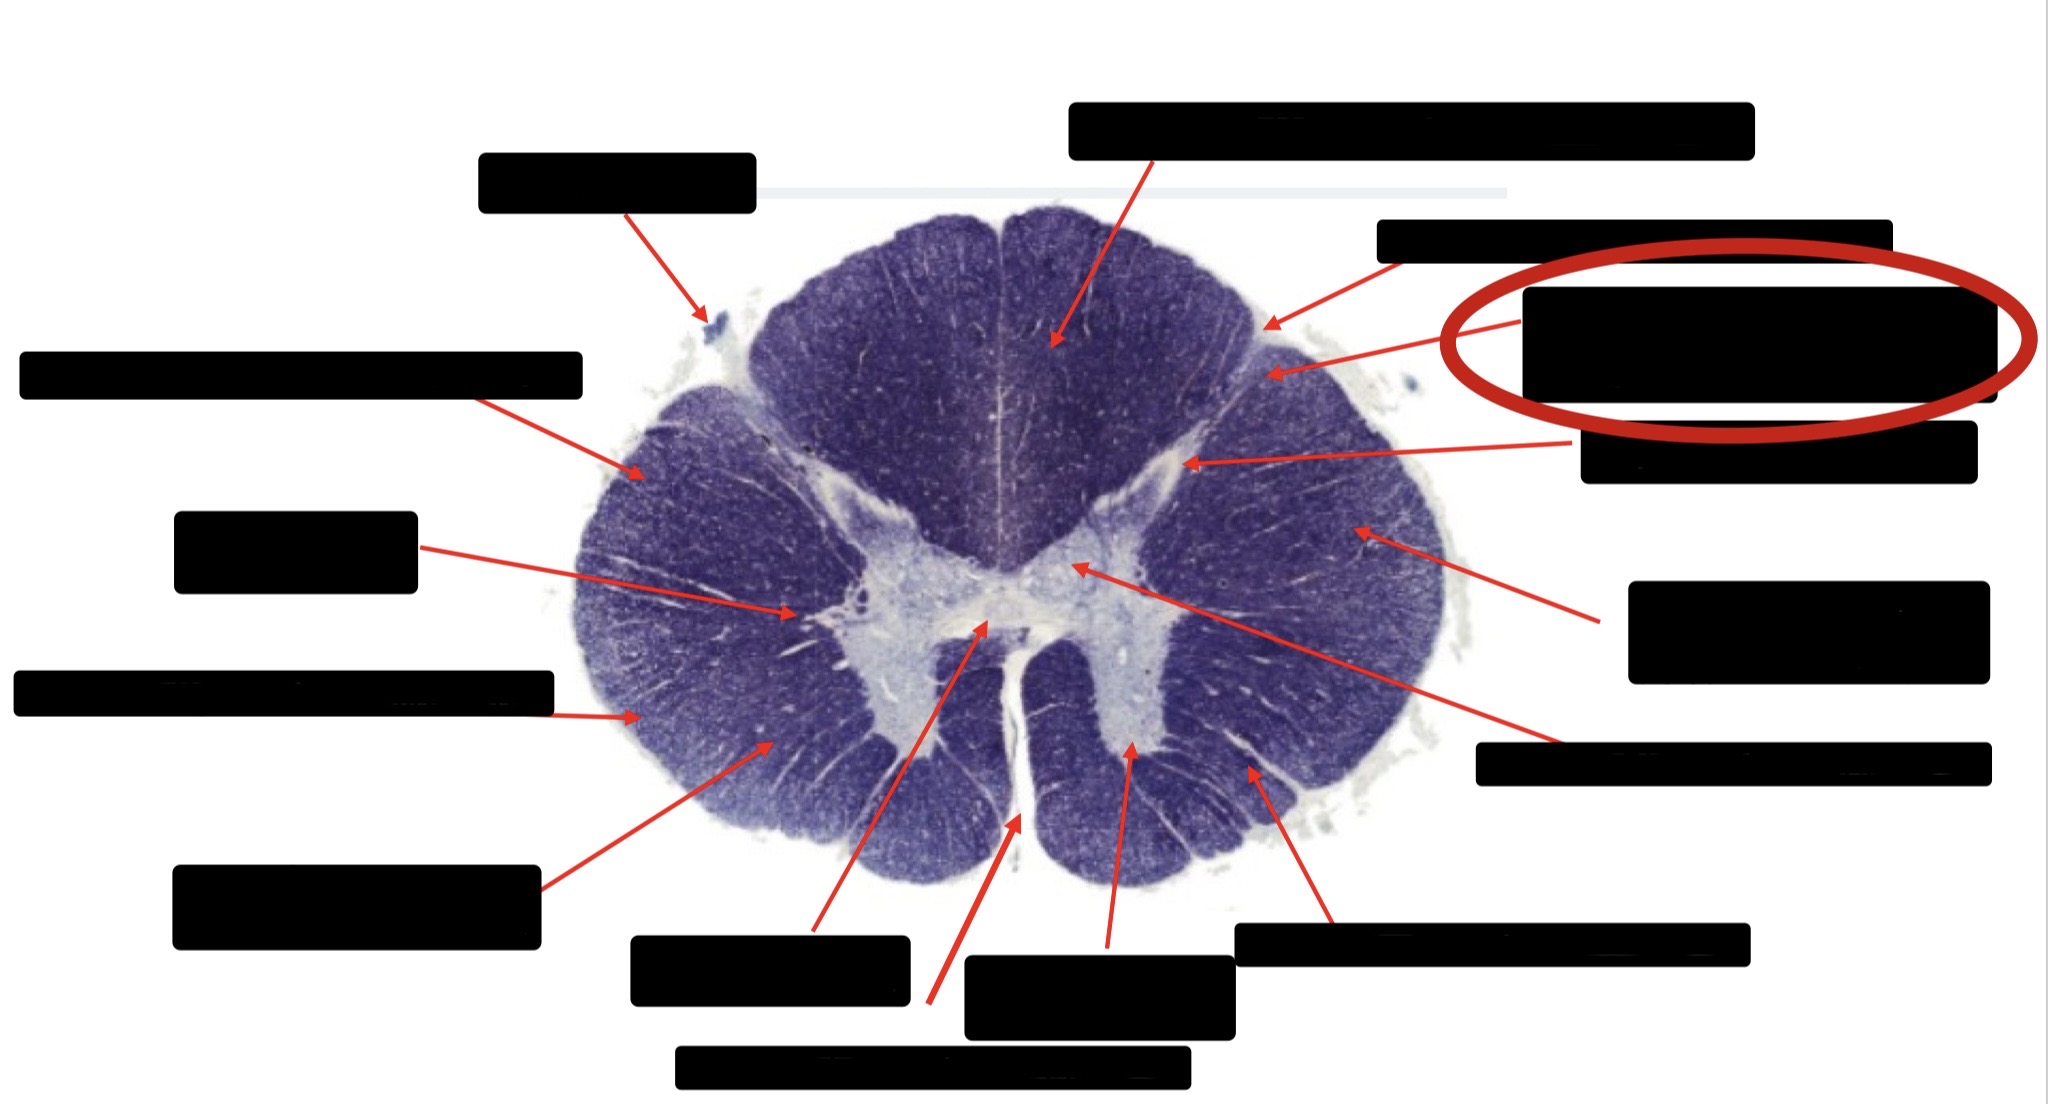

Central Canal

Anterior Corticospinal Tract

Posterior Column (Fasciculus Gracilis)

Posterior Column (Fasciculus Cuneatus)

Substantia Gelatinosa

Accessory Nerve Fibers

Anterior Horn Motor Fibers (Accessory Muscles)

Anterior Horn Motor Fibers (Proximal Muscles)

Ventral Root Fibers

Anterior Horn Motors Neurons (Proximal Muscles)